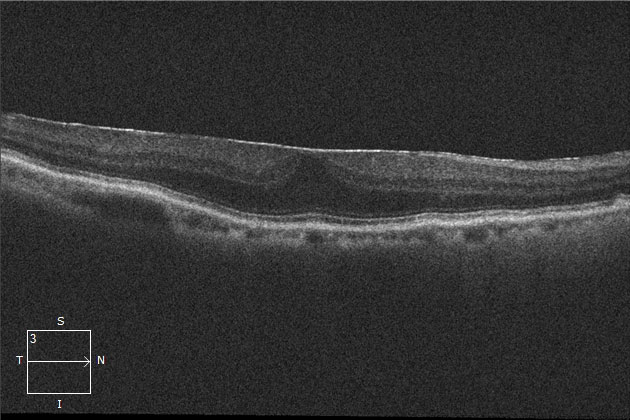

- OCT検査による画像

正常OCT

網膜前膜のOCT